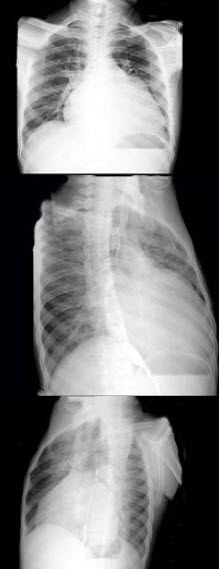

234、多项选择题

男,56岁,劳累后心慌气促10余年,近来自觉症状加重。临床听诊,心尖区有舒张期和收缩期杂音,行胸部X检查,如图所示,描述正确的是()

A.后前位示双房影,左心缘第三弓突出

B.右前斜位示左心房增大,心后上缘后突压迫服钡食管

C.左前斜位示心影向后下方突出

D.考虑三尖瓣狭窄

E.考虑二尖瓣狭窄并关闭不全